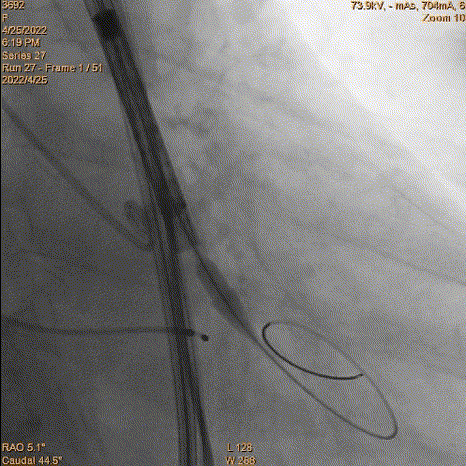

7、释放完成:第二次释放评估深度合适,缓慢释放脱钩,同轴性良好。撤递送系统,撤抓捕器。

二次评估深度

缓慢脱钩

术后结果:

超声显示支架内径21.5mm,有创压差12mmHg,使用23mm球囊后扩,术后血压115/74mmHg,右无融合处有微量瓣周漏。鉴于血流动力学、舒张压显示良好。没有瓣中瓣的必要。后续保持观察。综合评估,手术达到预期效果,复查通路没问题,结束手术。

23mm球囊后扩

最后造影

复查入路